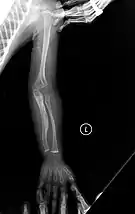

The main symptom of osteogenesis imperfecta is fragile, low mineral density bones; all types of OI have some bone involvement.[5] In moderate and especially severe OI, the long bones may be bowed, sometimes extremely so.[28] The weakness of the bones causes them to fracture easily—a study at the Endocrine Unit at the National Institute of Child Health in Karachi, Pakistan found an average of 5.8 fractures per year in untreated children.[29] Fractures typically occur much less after puberty, but begin to increase again in women after menopause and in men between the ages of 60 and 80.[1]: 486

OI type III causes osteopenic bones that fracture very easily, sometimes even in utero, often leading to hundreds of fractures during a lifetime;[24] early scoliosis that progresses until puberty; dwarfism (a final adult height frequently less than 4 feet or 120 centimetres); loose joints; and possible respiratory problems due to low rib cage volume causing low lung volumes.[5]: 1512

Diagnosis is typically based on medical imaging, including plain X-rays, and symptoms. In severe OI, signs on medical imaging include abnormalities in all extremities and in the spine.[97] As X-rays are often insensitive to the comparatively smaller bone density loss associated with type I OI, DEXA scans may be needed.[5]: 1514